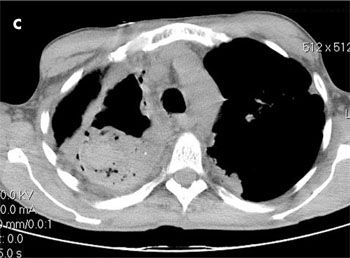

The patient was afebrile. Oxygen saturation was 99% on room air. Positive findings were dry inspiratory crackles and rhonchi in the right lung field, and a mobile, 1 x 1-cm, mildly tender right cervical lymph node. A chest radiograph revealed right apical pleural thickening involving the upper half of the right hemithorax, cavitation with an air-fluid level, emphysematous bullae, and scarring in the left upper lung (A). A CT scan of the chest showed a complex 7.6 x 6.2-cm cavity with thick and irregular walls in the right lung with volume loss and scarring (B and C). An extensive amount of heterogeneous material was located within the cavity. Scarring and bronchiectasis in the left upper lung and multiple lymph nodes (the largest, 2 x 2 cm) in the right hilum were also noted.